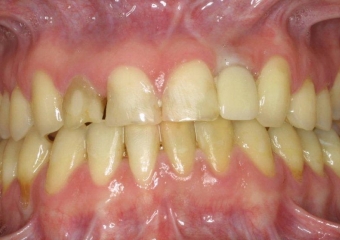

Sorriso inicial

Imagem inicial com ausencia do incisivo lateral esquerdo